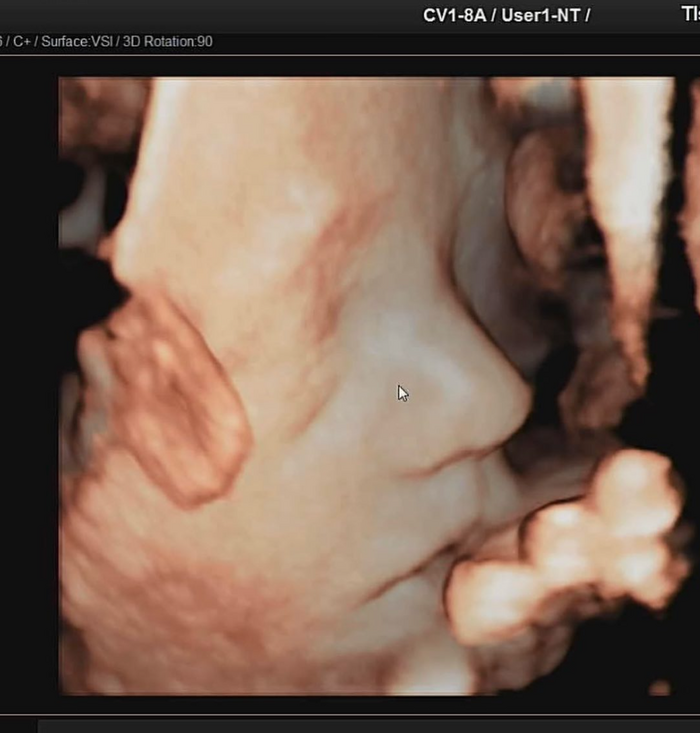

임현주는 30일 자신의 채널에 태명이 일월이인 아기의 초음파 사진을 공개했다. 조각상처럼 매끄럽고 오뚝한 콧날이 인상적인 사진이었다.

임현주는 “사진 잘 나오는 각도로 얼굴을 빼꼼 보여주었어요. 간접적으로나마 처음 보는 작은 인간의 얼굴이니 얼마나 떨리고 뭉클했는지”라며 설렘을 감추지 못했다.

임현주의 글에 누리꾼들은 “와우. 태아가 이런 코를 신기해요” “정말 이대로 나오는데. 일월이는 엄청 예쁘네”라는 반응이었다.